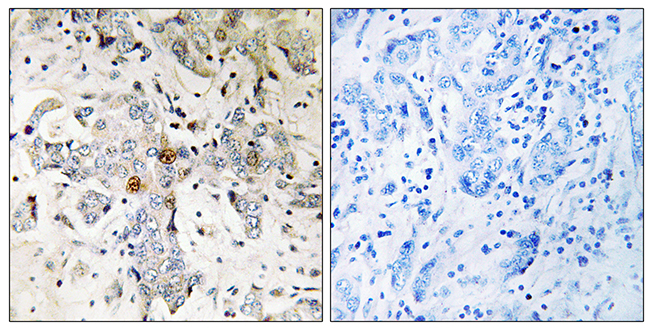

ApplicationsWestern Blot, ImmunoHistoChemistry

ReactivityHuman

- SizePrice